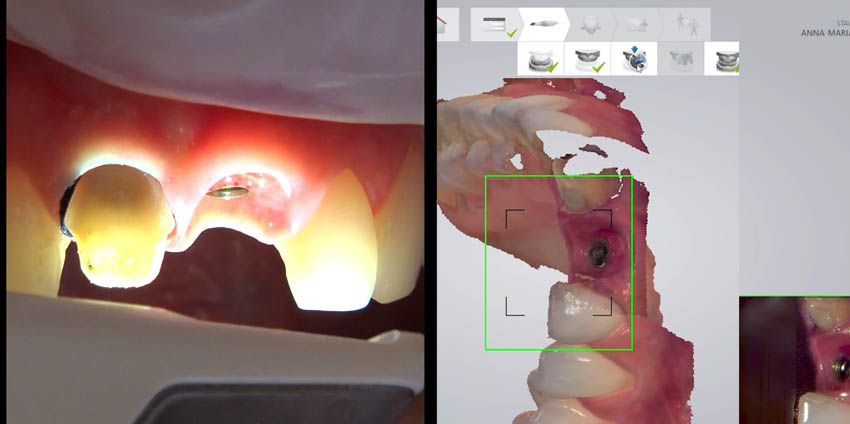

The synergy between digital and analog workflow. When and how?

Initial impression. Analog and digital workflow. CR registration using anterior deprogrammer.

LIVE presentation of cases with single implants. Single implant digital

Intraoral scanning: scanning protocol and precision